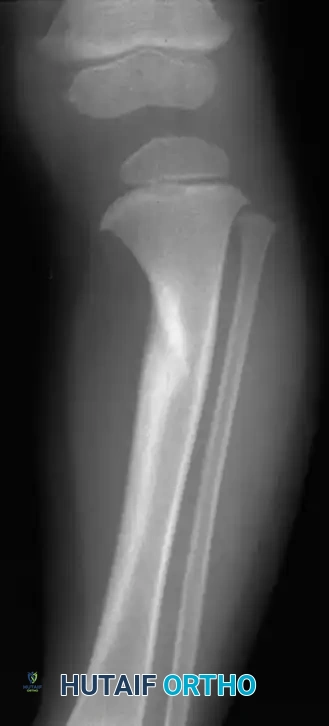

The infantile form begins before 8 years of age and is notoriously difficult to differentiate from physiological bowing, especially in children younger than 2 years. Infantile tibia vara is bilateral and symmetrical in approximately 60% of affected children, whereas physiological bowing is almost universally bilateral. The critical distinction lies in the natural history: in Blount disease, the varus deformity increases progressively, whereas physiological bowing tends to resolve spontaneously with growth.

Histological changes in late-onset tibia vara are markedly similar to those seen in infantile tibia vara and slipped capital femoral epiphysis (SCFE), suggesting a common mechanical etiology. Loder et al. reported that less than half of late-onset cases are bilateral. Patients typically present with knee pain, a gradually progressive genu varum deformity, and an average preoperative tibiofemoral angle of 14 degrees.

In tibia vara, the medial half of the epiphysis is characteristically short, thin, and wedged. The physis is irregular in contour and slopes medially. The proximal metaphysis forms a distinct medial projection (metaphyseal beak). While this projection is palpable clinically, it is not exclusively diagnostic of tibia vara. However, medial metaphyseal fragmentation is considered pathognomonic for progressive disease.

Langenskiöld described the progressive epiphyseal changes and deformity through six distinct stages (Stages I–VI) correlating with growth and development. By Stage VI, the medial portion of the epiphysis fuses at a 90-degree downward angle, representing a severe, irreversible physeal arrest.

To differentiate infantile Blount disease from physiological bowing, the metaphyseal-diaphyseal angle (Drennan’s angle) is a critical early indicator. Formed by a line drawn perpendicular to the longitudinal axis of the tibia and a line drawn through the two beaks of the metaphysis, an angle of 11 degrees or more is highly predictive of Blount disease. Children with angles less than 11 degrees typically have physiological bowing that resolves with growth.